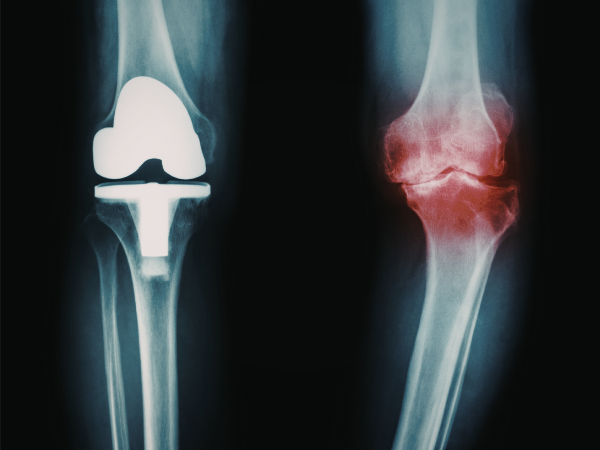

Wann ist eine OP nötig?

Eine Operation wird in der Arthrosebehandlung erst dann erwogen, wenn konservative Maßnahmen über mehrere Monate keine ausreichende Linderung bringen. Typische Indikationen sind:

- Starke, anhaltende Schmerzen trotz Physiotherapie, Bewegung und medikamentöser Therapie

- Deutliche Gelenkfehlstellungen oder Instabilitäten

- Eingeschränkte Beweglichkeit, die den Alltag erheblich beeinträchtigt

- Fortschreitender Knorpelabbau oder mechanische Gelenkblockaden

Ziel einer Operation ist nicht nur Schmerzlinderung, sondern auch Wiederherstellung der Gelenkfunktion und Belastbarkeit.